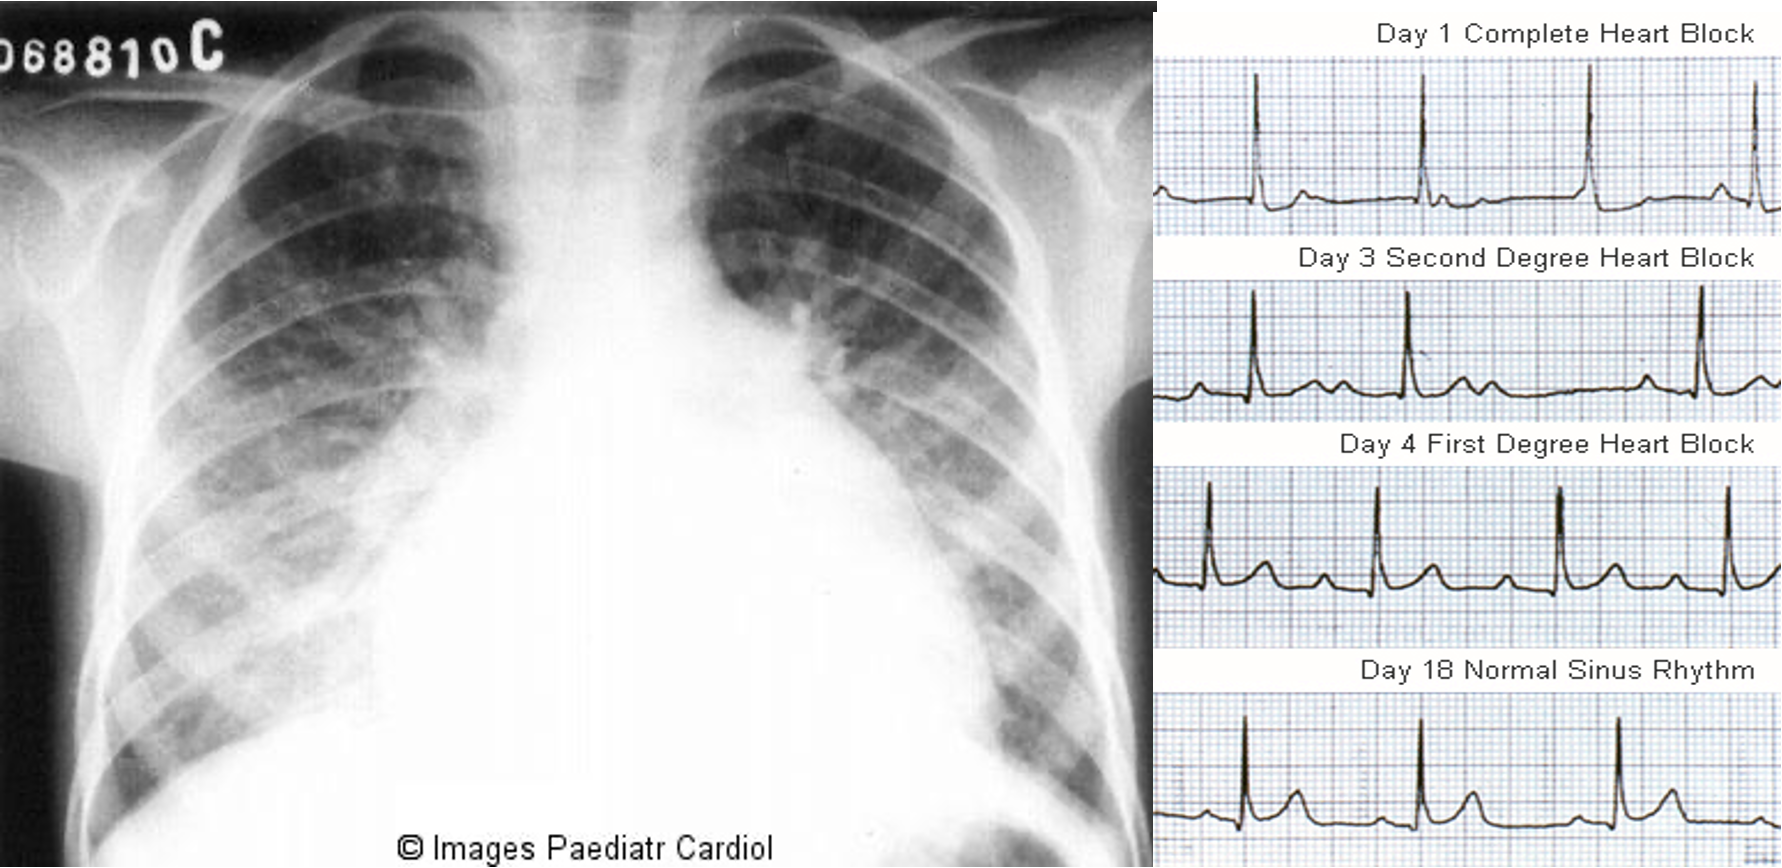

- Myocarditis: Cardiomegaly, CHF, Sinus tachycardia, heart block. Rapid sleeping pulse rate.

Chest radiograph of an 8 year old patient with acute carditis before treatment

Chest X ray: Cardiomegaly, pulmonary congestion, and other findings consistent with heart failure may be seen on chest radiography.

ECG: prolonged PR interval, 2nd or 3rd degree blocks,ST depression, T inversion